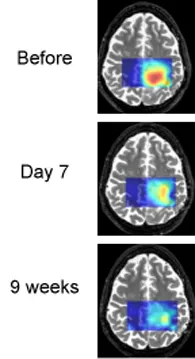

Tumor cells often produce an excess of lactic acid. MRS brain scans show that lactic acid levels are decreasing as treatment proceeds. This patient is an example of a "good responder."

Winship Cancer Institute researchers are testing an experimental therapy for glioblastoma, the most common and most aggressive form of primary brain cancer. The study uses brain imaging in an effort to detect whether the therapy is having an effect after one week.

The therapy combines vorinostat, an experimental drug, with temozolomide, which is standard treatment for glioblastoma.“Vorinostat is a different type of cancer drug,” says Hyunsuk Shim, PhD, associate professor of radiology at Emory University School of Medicine. “It’s an epigenetic therapy, and the desired effect is to turn genes that could suppress tumor growth back on. One of the desired effects is to restore normal metabolic behavior to the cancer cells, halting tumor growth.”

In this National Cancer Institute (NCI)-sponsored clinical trial, the researchers are using magnetic resonance spectroscopy (MRS) to detect changes in brain metabolism brought on by vorinostat. MRS, a form of imaging similar to MRI, allows doctors to monitor the levels of several brain chemicals. The researchers will gauge the levels of inositol and N-acetylaspartate, which are both indicators of healthy brain metabolism.